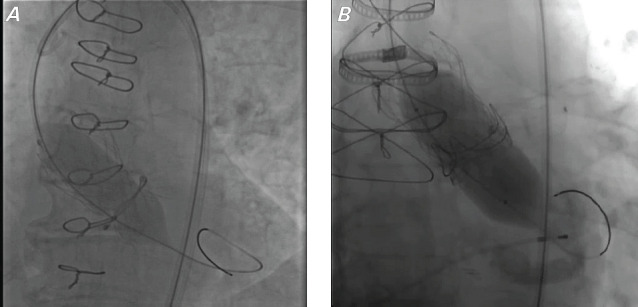

Methods: Patients with a history of surgical aortic valve replacement undergoing ViV-TAVI bioprosthetic valve fracture (N = 25) at the corresponding institution from 2015 to 2022 were cataloged for a retrospective analysis. The implanted transcatheter valves were Medtronic Evolut R, Evolut PRO, and Evolut PRO+. Gradients were assessed before and after implantation and after fracturing using transthoracic echocardiogram.